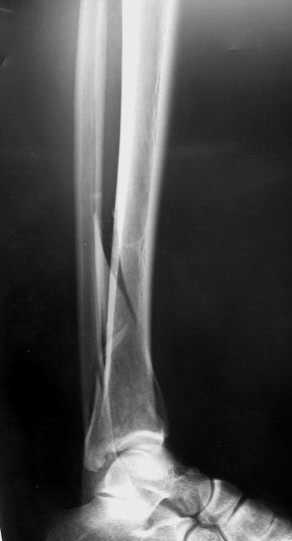

Уважаемые коллеги! Внутрисуставной перелом дистального конца б/б кости со смещением и подвывихом стопы должен был лечиться оперативно в раннем сроке.

Пример - довольно похожий перелом, оперированный в первые 8 часов после аварии у 40-летнего больного, страдающего тяжёлым сахарным диабетом 1 типа.